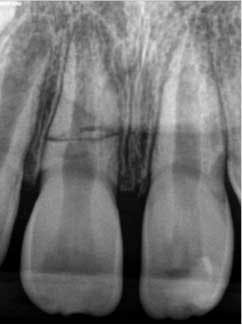

A 7-year-old male presented to my office following an accident that resulted in a horizontal root fracture of tooth No. 8. Upon examination, the general dentist had splinted the central incisors together using a rigid splint. Clinical testing on tooth No. 8 revealed that this tooth had a nonlingering response to cold and displayed slight tenderness to palpation. All other testing on teeth Nos. 7 and 9 was within normal limits (WNL). Radiographically, the apices of both central incisors were incompletely developed and a horizontal root fracture was noted at the junction of the coronal and middle third of the root on tooth No. 8 (figure 1). Due to the positive response to cold and lack of symptoms to percussion, bite, and palpation, I recommended retesting in three weeks and removal of the splint.